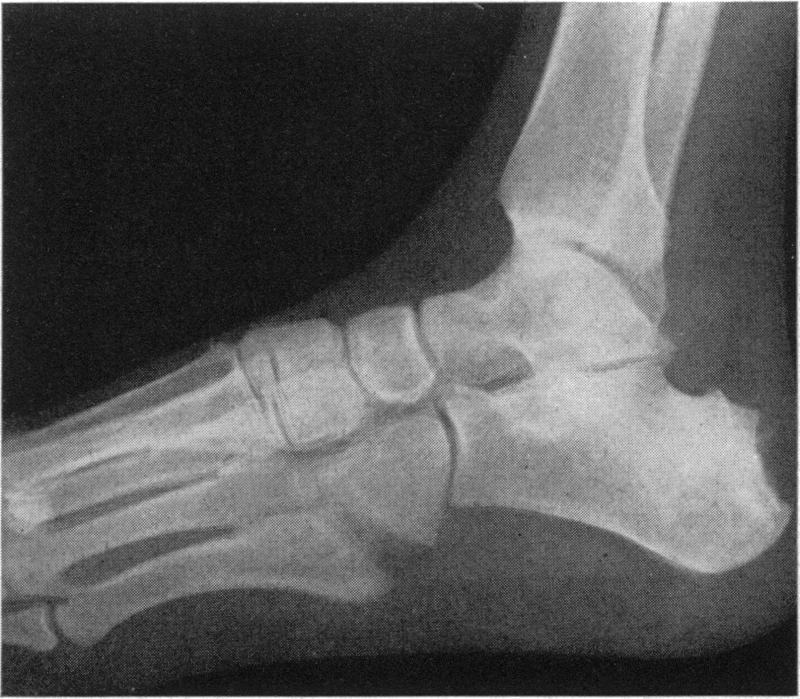

A form of endemic syphilis exists in the Bakwena Reserve of the Bechuanaland Protectorate known by the local name of "dichuchwa". It is similar to bejel, njovera and the endemic syphilis reported elsewhere in the world. The Government of the Protectorate, with the assistance of WHO and UNICEF, began in November 1953 a mass campaign in the Reserve to control this disease and, at the same time, to study its epidemiological, clinical, social and therapeutic aspects. The seropositivity rate in the Reserve was found to be 37%.Dichuchwa is a childhood and family disease, usually spread non-venereally. The early lesions are similar to secondary lesions of sporadic venereal syphilis, and are often followed by tertiary lesions affecting mainly the skin, nasopharynx and long bones. Primary lesions are rare but may occur under certain epidemiological conditions if the inoculum is sufficiently large; thus a mother may develop primary sores on the nipples through suckling an infected infant. Lesions of the cardiovascular and central nervous systems and congenital syphilis are also rare. Superinfection of an already infected and allergic host is probably the chief reason for the frequency of the tertiary lesions.Treatment of the disease with penicillin is very effective, and the authors believe that mass treatment of cases and contacts combined with an improvement in the standards of hygiene could eradicate the disease.

在贝专纳兰保护地的巴克韦纳保护区存在一种地方性梅毒,当地称之为“迪楚瓦病”。它与非性病性梅毒、恩乔韦拉病以及世界其他地方报道的地方性梅毒相似。在世界卫生组织和联合国儿童基金会的协助下,保护地政府于1953年11月在该保护区发起了一场大规模防治这种疾病的运动,同时研究其流行病学、临床、社会和治疗方面的情况。发现该保护区的血清阳性率为37%。迪楚瓦病是一种儿童和家庭疾病,通常通过非性途径传播。早期损害类似于散发性性病梅毒的二期损害,随后常出现三期损害,主要影响皮肤、鼻咽和长骨。一期损害很少见,但在某些流行病学条件下,如果接种量足够大,也可能发生;例如,母亲在哺乳感染婴儿时,乳头可能出现一期溃疡。心血管和中枢神经系统损害以及先天性梅毒也很少见。已经感染且过敏的宿主发生重复感染可能是三期损害常见的主要原因。用青霉素治疗这种疾病非常有效,作者认为对病例和接触者进行大规模治疗并提高卫生标准可以根除这种疾病。